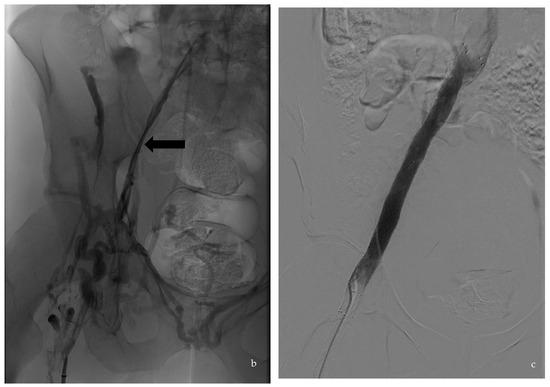

Figure 1.

Case of a 33-year-old patient with thrombophilic disease whose first DVT was diagnosed in 2013. He displayed PTS. (a) is a transversal slice of a CT scanner that shows the baseline phleboscanner with a collapsed left external iliac vein (black arrow) compared to the collateral one (white arrow) confirmed on (b), which shows phlebography assessment in a posterior incidence (black arrow). The treatment consisted of an angioplasty/stenting of the iliofemoral vein by popliteal vein approach, the results of which are displayed on the digital subtraction angiography (c).